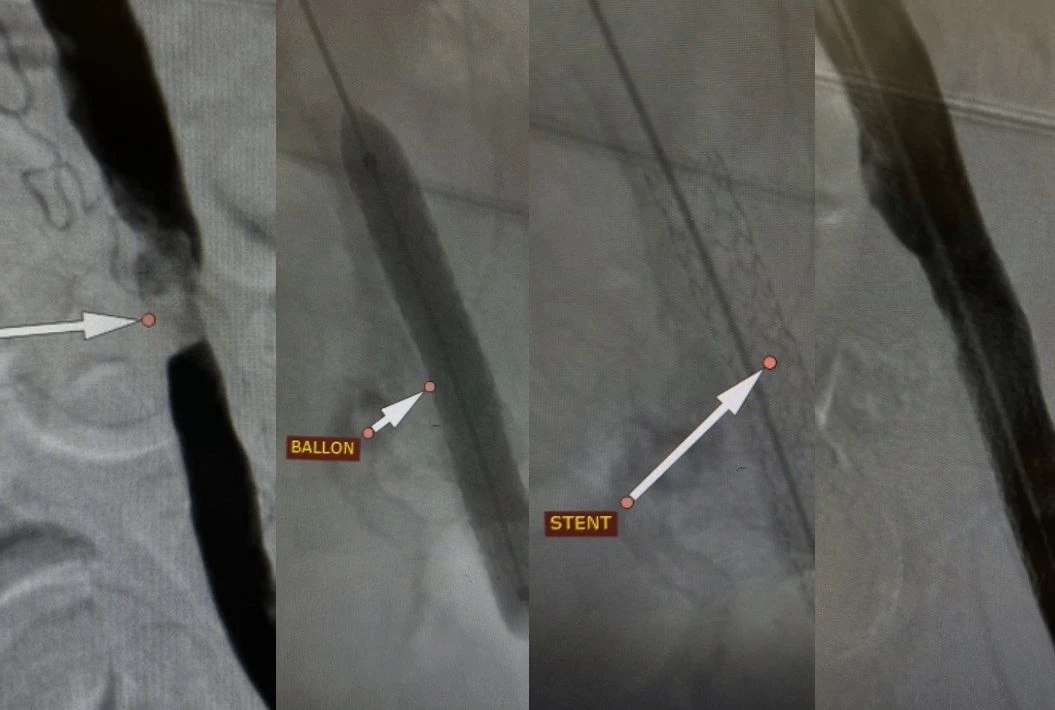

В волгоградской больнице провели сложную операцию на ноге. Пациента спасли от ампутации конечности.

В связи с противопоказаниями к классическому виду операции было принято решение провести рентгенэндоваскулярное вмешательство, которое стало единственным шансом сохранить ногу.

Через небольшой прокол в бедренной артерии врачи выполнили стентирование подвздошной артерии для поддержания просвета сосуда. Спустя сутки пациент смог самостоятельно передвигаться и покинул стационар.